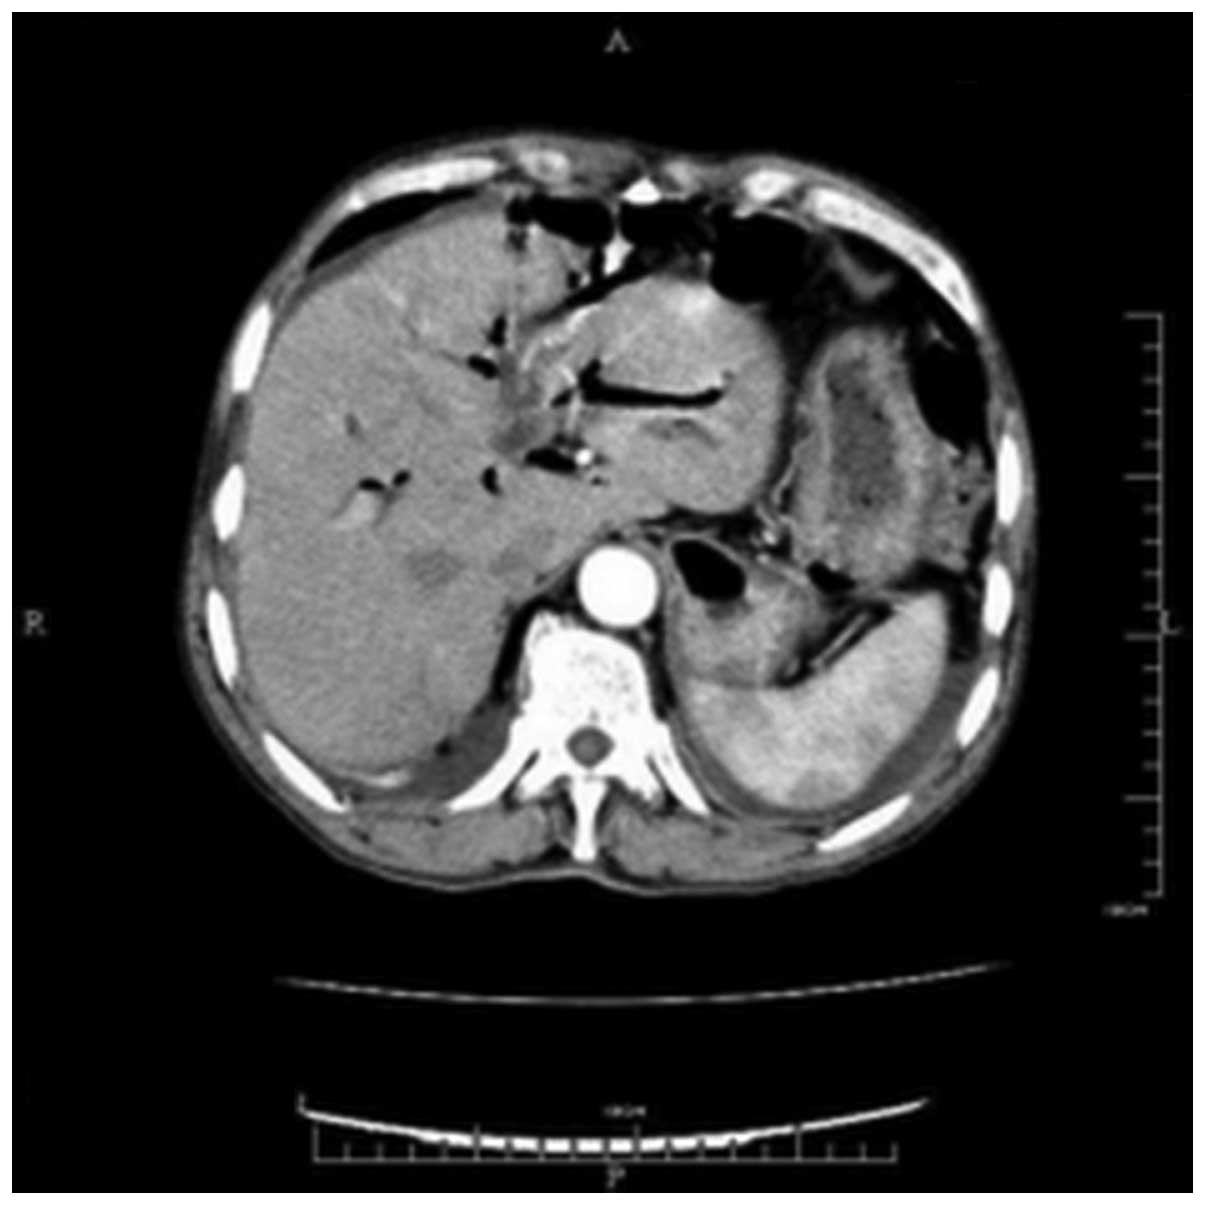

The patient's abdomen was soft, with slight tenderness in the upper region. The laboratory results showed anemia (hemoglobin, 62 g/l; normal range, 120–160 g/l) and hypoproteinemia (albumine 23 g/l; normal range, 35–55 g/l), with total bilirubin (normal range, 0–21µmol/l), alanine aminotransferase (normal range, 5–35 U/l) and aspartate transaminase (normal range, 8–40 U/l) levels that were all within the normal ranges. Anti-hemorrhagic (hemocoagulase atrox for injection, 4 units/day, intravenous injection) and antibiotic treatments (Cefodizime Sodium, 2 g/day, intravenously guttae) were commenced. Abdominal ultrasound and magnetic resonance cholangiopancreatography showed multiple low-echo occupations and a stripe echo in the common bile duct, with dilatation of the intrahepatic and extrahepatic bile ducts. Abdominal computed tomography revealed stones in gallbladder and right liver with air in dilated intrahepatic and extrahepatic bile duct (Fig. 1). Suspecting that the bleeding was associated with the inflammation of the bile duct, endoscopic retrograde cholangiopancreatography (ERCP) was performed to find the position and the etiology of the bleeding. However, during the examination, the scope could not be passed through the obstructed section of deformed pylorus, and no significant abnormality of tract was found above the pylorus. Therefore, gastroduodenography was performed, which showed contrast medium entering into the bile tract (Fig. 2). Accordingly, upper GI bleeding and pyloric obstruction, with cholangitis secondary to a CDF was considered. Following anti-hemorrhagic and antibiotic treatments, the symptoms of fever and abdominal pain were relieved.

Figure 1.

Abdominal computed tomography showing pneumobilia in the intrahepatic bile duct.